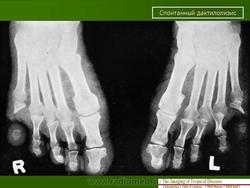

Аингум (ainhum) - спонтанный дактилолизис, описал Da Silva Lima (1852,1867).

Клиника аингума проявляется в виде кольцевидной перетяжки различной ширины с явлениями склероза преимущественно в области пятых пальцев стоп, иногда кистей. В результате дегенерации жировой и фиброзной тканей, постепенного рассасывания кости через 3-5 лет происходит спонтанная безболезненная ампутация пальца.